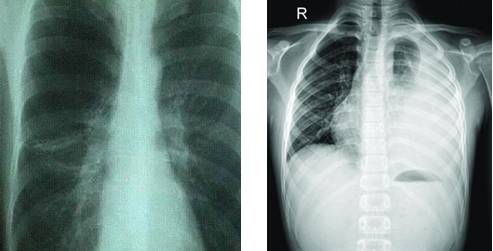

答案是否定的。怀孕期间因诊断的需要可能接受的放射性诊断措施有X线照射(如上图),超声波,核磁共振,CT扫描,或者核医学诊断。其中,X线照射是最常见也是最容易引起孕妇和家属惊恐的。

根据美国放射协会和妇产协会的数据,孕妇接受单次胸部X线检查腹中胎儿受到的照射剂量为0.02–0.07毫rad。记住,高于5000毫rad才会造成胎儿损伤,也就是说要至少连续拍5000÷0.02=250000张或5000÷0.07=71428张胸部平片才可能造成胎儿损伤。单次腹部X线平片胎儿受到的照射量为100毫rad(5000÷100=50次),肾盂静脉造影胎儿受到的照射量可能大于1 rad(1000毫rad)。

头胸部CT检查胎儿受到的照射量小于1 rad。

也就是说,普通X线平片通常只会暴露胎儿于非常小的照射剂量。而且通常孕期需要做X线检查时候,孕妇的腹部是会用含有铅的防护衣保护起来的,更进一步降低受照剂量,其实基本是0辐射。除开钡灌肠和小肠连续成像,绝大多数造影剂荧光检查也只会给胎儿带来毫rad的剂量。CT造成的照射依照射数量和成片距离会有不同。盆腔CT可能会给胎儿带来高达1.5 rad的照射,但放射科医生通过使用低剂量技术是可以将它降低到接近250毫rad的(相当于5000÷250=20次CT扫描的剂量),但是CT医师是不会像疯子一样连续同一个部位扫20次的。

常规齿科X线检查,头部X线检查,四肢X线检查,以及胸部X线检查,包括乳腺钼靶检查,或者头胸部CT是不会对胎儿造成损伤的,儿童期癌症的风险提高也可以轻忽不计。需要做腹部检查时请与医生商量。